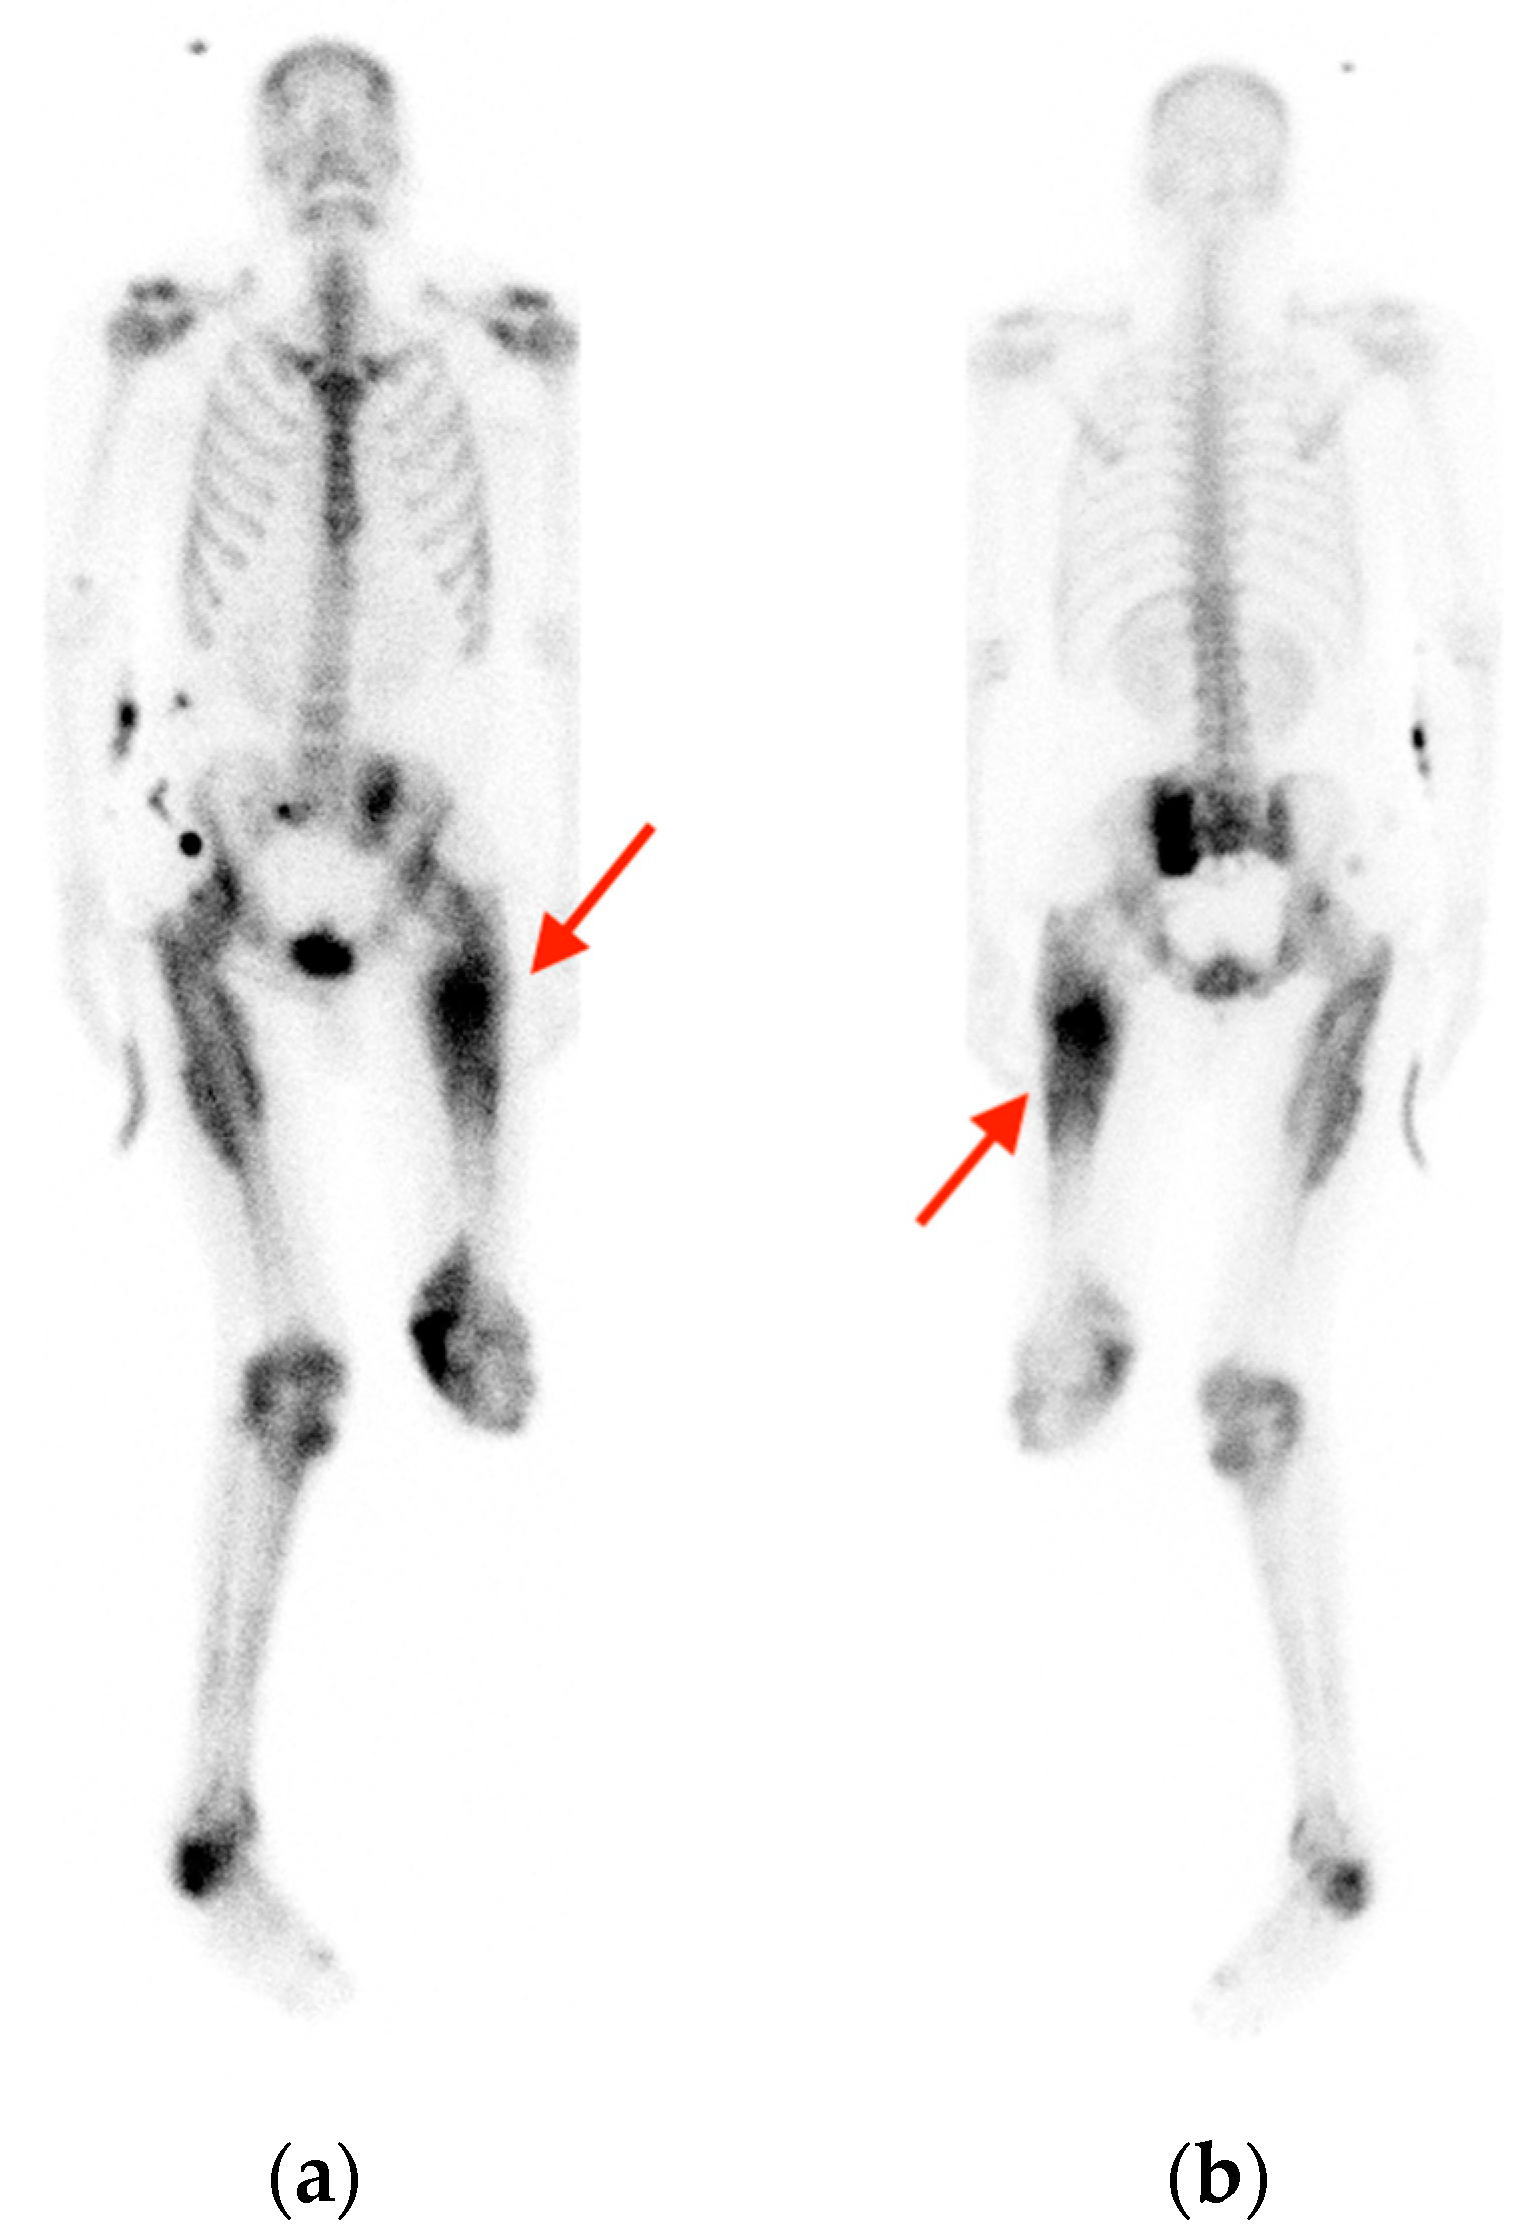

2.3. Enchondroma

- Mulligan, M.E. How to Diagnose Enchondroma, Bone Infarct, and Chondrosarcoma. Curr. Probl. Diagn. Radiol. 2019, 48, 262–273. [Google Scholar] [CrossRef] [PubMed]

- Cheung, H.; Yechoor, A.; Behnia, F.; Abadi, A.B.; Khodarahmi, I.; Soltanolkotabi, M.; Shafiei, M.; Chalian, M. Common Skeletal Neoplasms and Nonneoplastic Lesions at 18F-FDG PET/CT. Radiographics 2022, 42, 250–267. [Google Scholar] [CrossRef]

- Subhawong, T.K.; Winn, A.; Shemesh, S.S.; Pretell-Mazzini, J. F-18 FDG PET differentiation of benign from malignant chondroid neoplasms: A systematic review of the literature. Skelet. Radiol. 2017, 46, 1233–1239. [Google Scholar] [CrossRef]